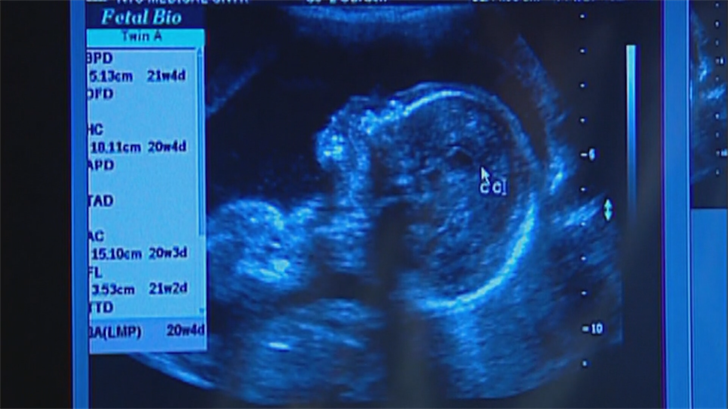

Based on the county’s Fetal Infant Mortality Reviews, he said, one of the biggest issues impacting infant mortality rates is prenatal care.

“It’s so very important to get connected with your OBGYN, with a healthcare provider during that first trimester, because that truly sets the foundation for a healthy pregnancy and a healthy child,” Tekac said in an interview Thursday.